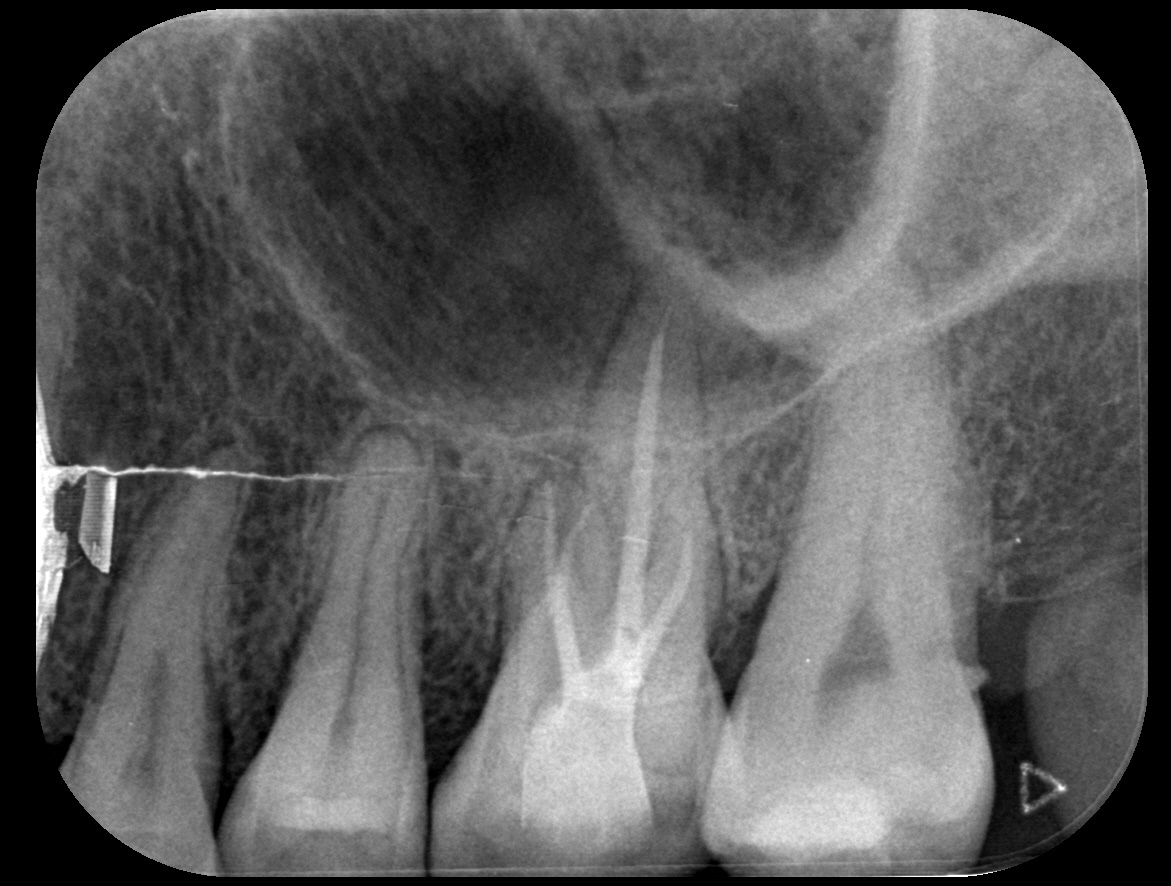

일반진료

BEFORE & AFTER